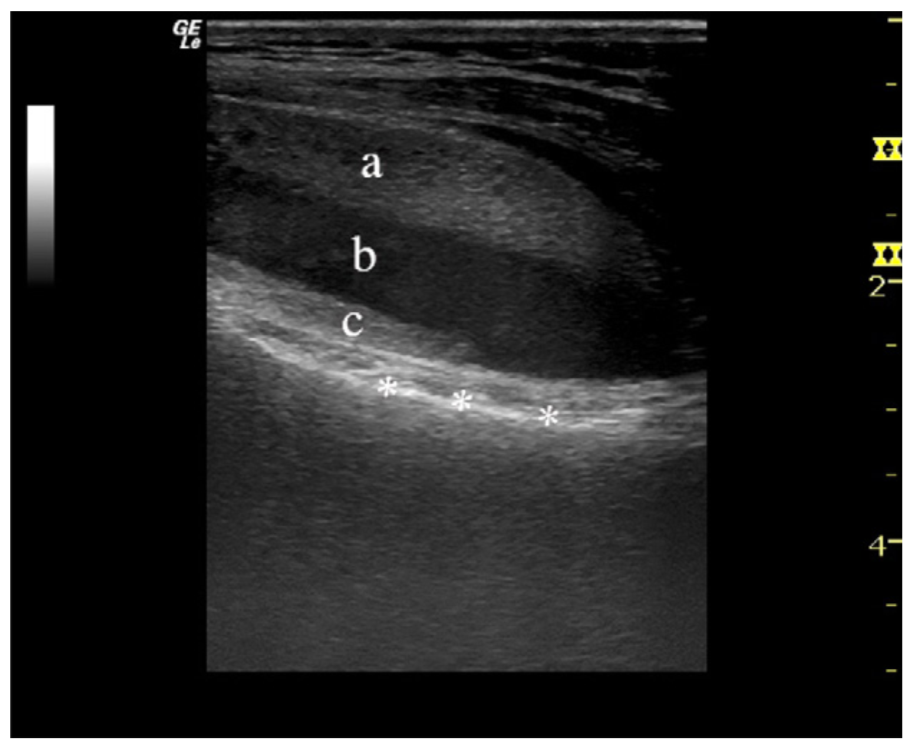

病例3 在超声上和MR上,均可见明显液体分层。